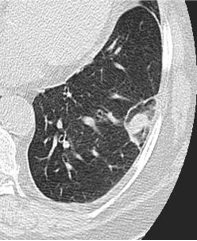

Most often used technique for FU after ablation of a lung tumor

Ablation zone: increase in size in the early postoperative period

inflammatory changes, hemorrhagic phenomenon, … and safety margins

Before 6 months: RF or MW ablation zone is supposed to exceed the size of the initial tumor (complete ablation).

After 6 months: the scar decreases in size (complete ablation), But may remain stable. Long term FU: scar equal or bigger than the initial tumor.